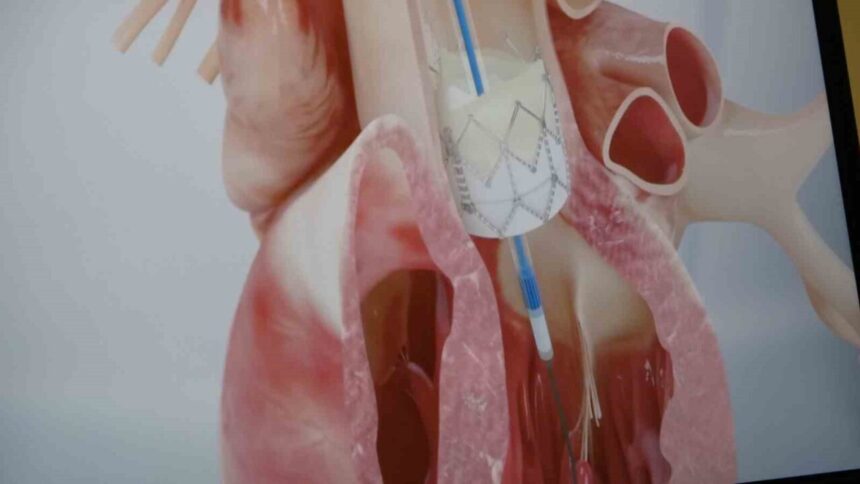

Koroner arter hastalığının dünya genelinde ölümlerin en önemli sebeplerinden biri olduğunu vurgulayan Prof. Dr. Pekdemir, “Koroner arter hastalığı, kalp damarlarının yaşlanması ve kireçlenmesiyle gelişiyor. Ancak gençlerdeki ani ölümlerin büyük bir kısmı genetik faktörlerden kaynaklanıyor. Gençlerde görülen ani ölümlerin nedenleri arasında koroner arter anomalileri, doğuştan kalp kası hastalıkları, hipertrofik kardiyomiyopati, uzun QT sendromu, Brugada sendromu, geçirilmiş viral enfeksiyonlar ve bazı ilaç veya uyuşturucu kullanımları yer alıyor” ifadelerini kullandı.